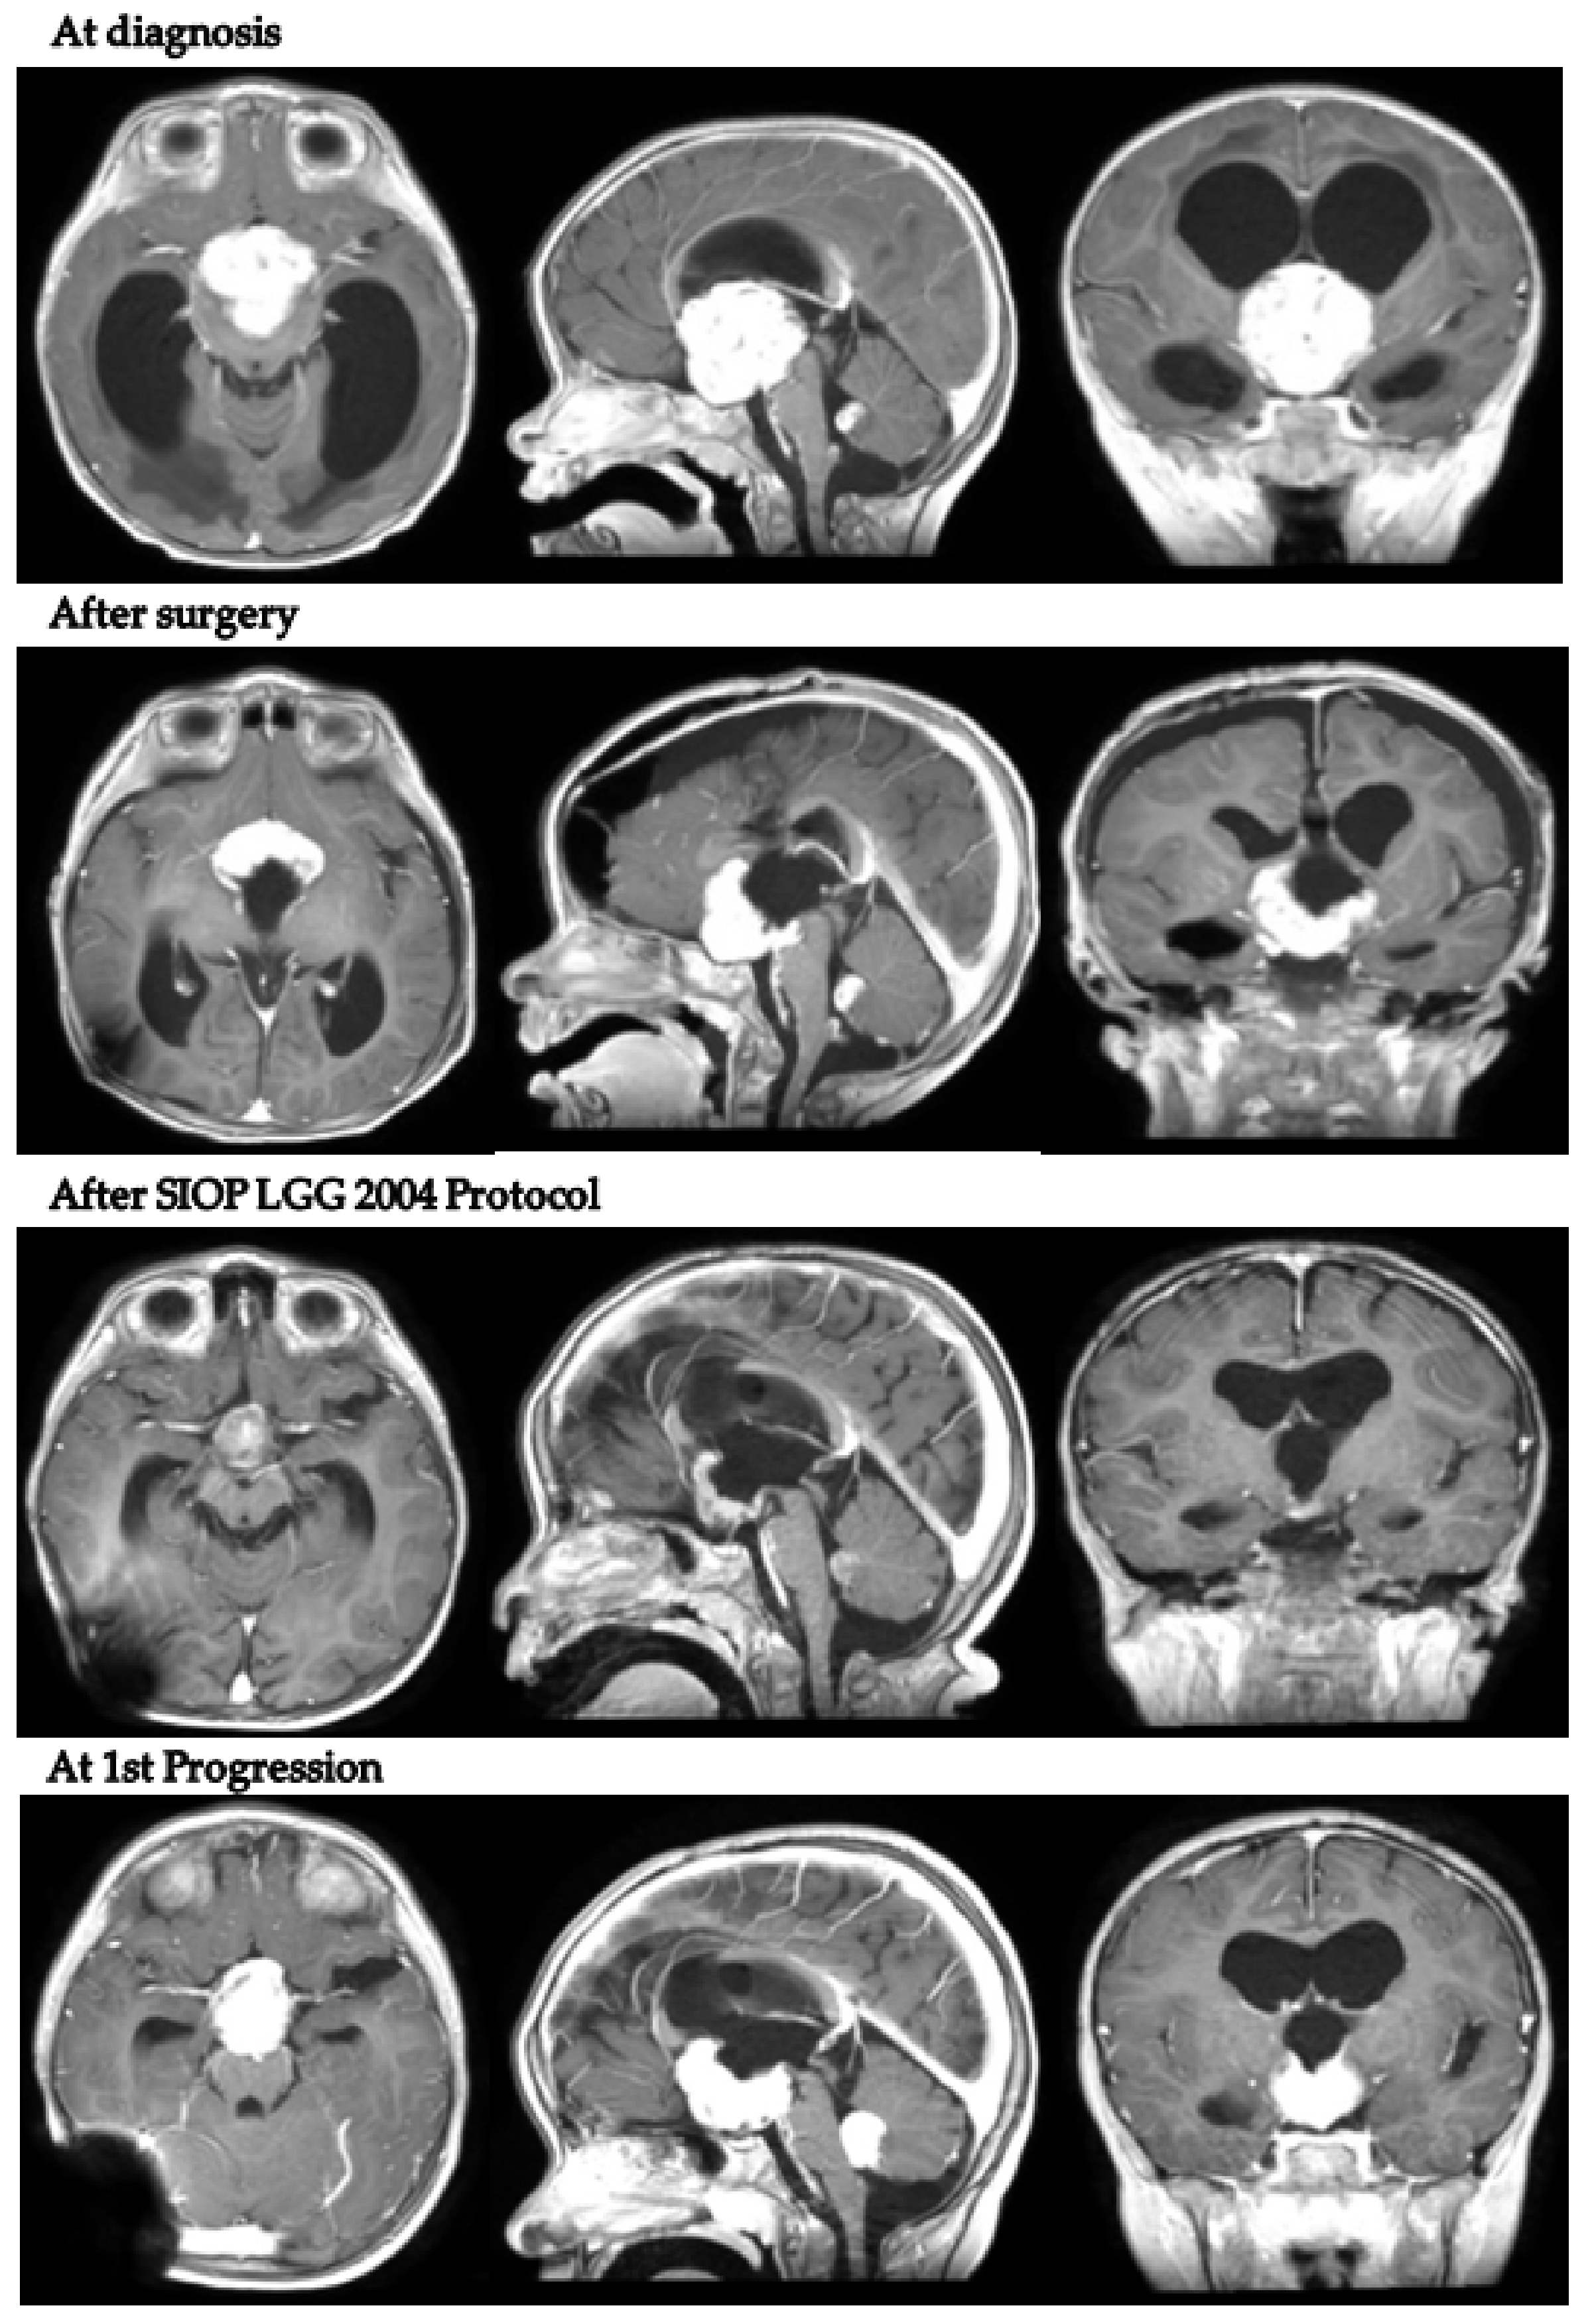

In detail, patient 5 presented with hydrocephalus at 17 months old and was diagnosed with a hypothalamo-chiasmatic PXA BRAF V600E mutation. A vincristine/carboplatin regimen was initiated. The end of treatment MRI demonstrated a reduction in tumor volume. However, six months later, neuroradiological progression was documented (Figure 4). Second-line treatment with dabrafenib and trametinib was subsequently started and is still ongoing.

Figure 4.

Patient 5 axial, coronal and sagittal post-contrast T1-weighted MRI scans at 4 different timepoints.